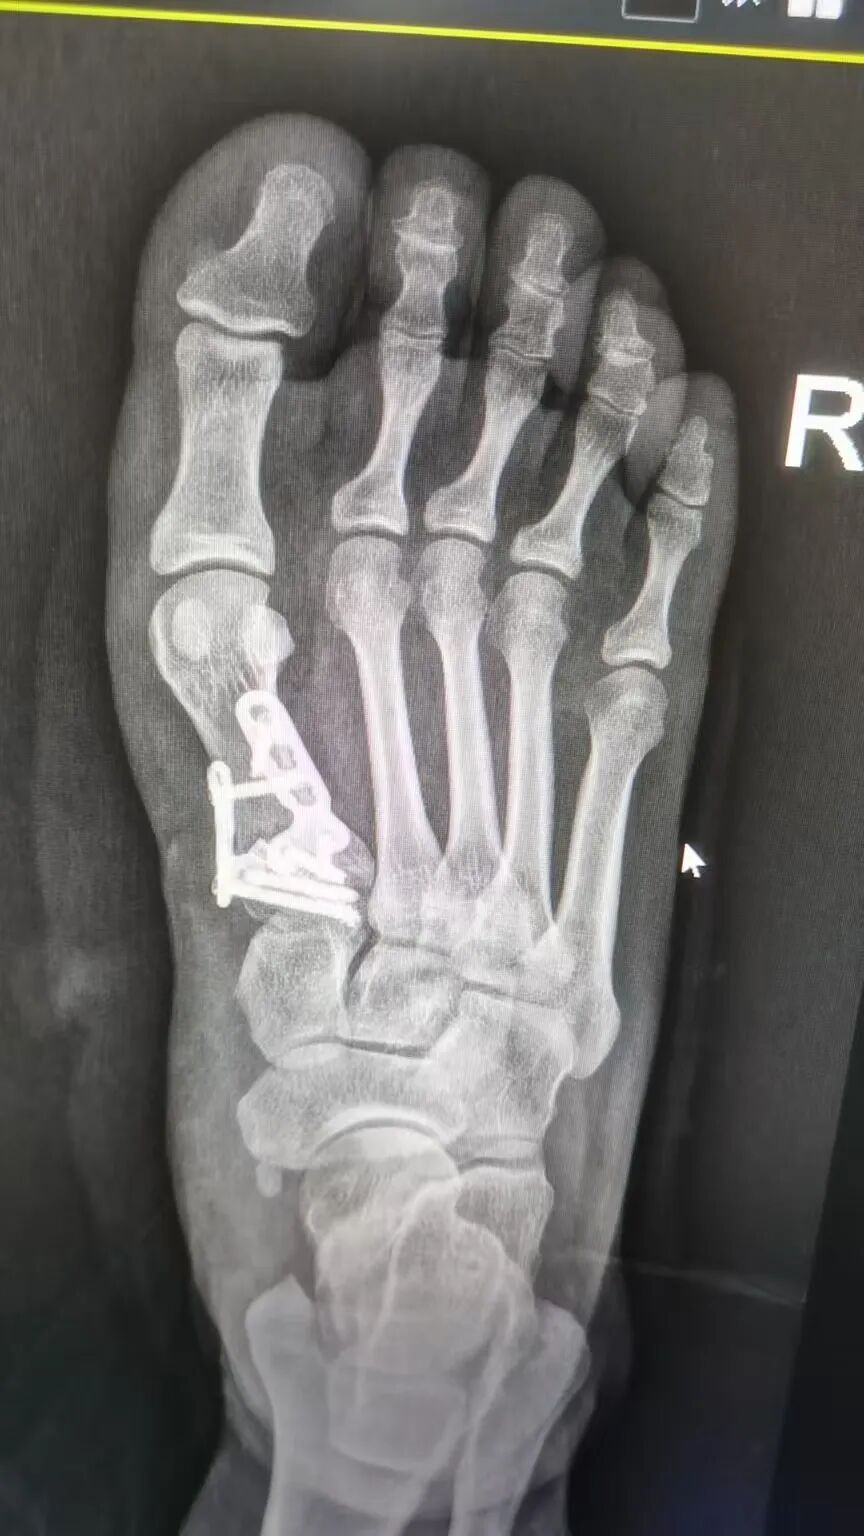

经过两个礼拜的精心治疗与护理,唐女士的手术非常成功,病情得到了显著改善而康复出院。为表达感激之情,她特意写下这封感谢信,字里行间满是对医护人员专业素养的认可和人文关怀的动容。

△术后